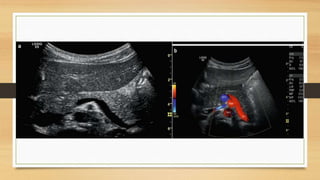

• #57 (a) The splenic vein can be imaged behind the body and tail of the pancreas in B-mode. Transverse section through the upper abdomen. (b) Colour Doppler of the flow in the splenic vein in a transverse section through the upper abdomen. The flow in the splenic vein (SV) along the pancreatic tail is directed towards the transducer and therefore displayed red. Close to the pancreatic head, the flow in the splenoportal confluence (SPC) is directed away from the transducer and therefore displayed blue. The aorta (DAO), the inferior vena cava (IVC), right renal artery (RA) and the superior mesenteric artery (SMA) are shown.